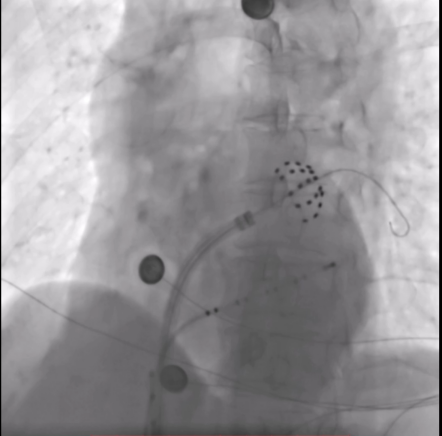

(花瓣状消融) (网篮状消融)